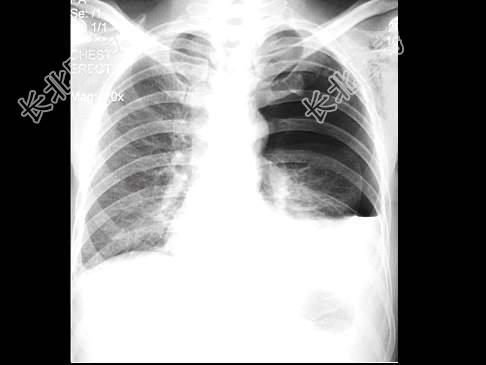

- 单项选择题男,32岁, 2天前被人踢伤胸部,感胸闷、呼吸困难, X线检查如图,最可能的诊断为 ( )

A、左侧气胸

B、左侧胸腔积液

C、左侧胸膜肥厚

D、左侧液气胸

E、左侧肺挫伤